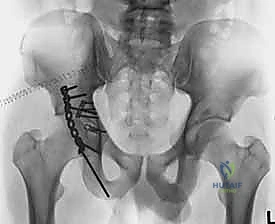

5. التثبيت الداخلي (Internal Fixation)

بعد التأكد من الرد المثالي باستخدام الأشعة داخل العمليات، يتم تثبيت الكسر بشكل نهائي.

* يتم استخدام مسامير معدنية (Screws) لتثبيت الشظايا الكبيرة.

* يتم وضع شرائح معدنية داعمة (Reconstruction Plates) على طول الجدار الخلفي والعمود الخلفي لتوفير دعم ميكانيكي قوي يمنع انزلاق الشظايا ويتحمل الضغط. يتم تشكيل هذه الشرائح يدوياً أثناء العملية لتطابق الانحناءات الطبيعية لحوض المريض.

* في بعض الحالات، تُستخدم تقنية "الشرائح الزنبركية" (Spring plates) لتثبيت الشظايا الصغيرة جداً التي لا يمكن وضع مسامير فيها.